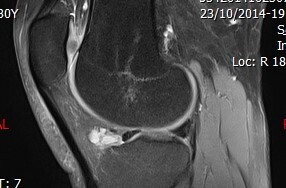

Compte tenu de la symptomatologie pauvre mais de la gêne fonctionnelle, une IRM du genou droit est effectuée, retrouvant un kyste mucoïde de la face antérieure du ménisque externe de 20 mm de grand axe (figure). La patiente a bénéficié d’une synovectomie antérieure sous arthroscopie, permettant d’amender ses douleurs.

• l’IRM est devenue l’examen de référence. Le kyste mucoïde se caractérise par un signal hypo-intense en T1 et hyperintense en T2 ;